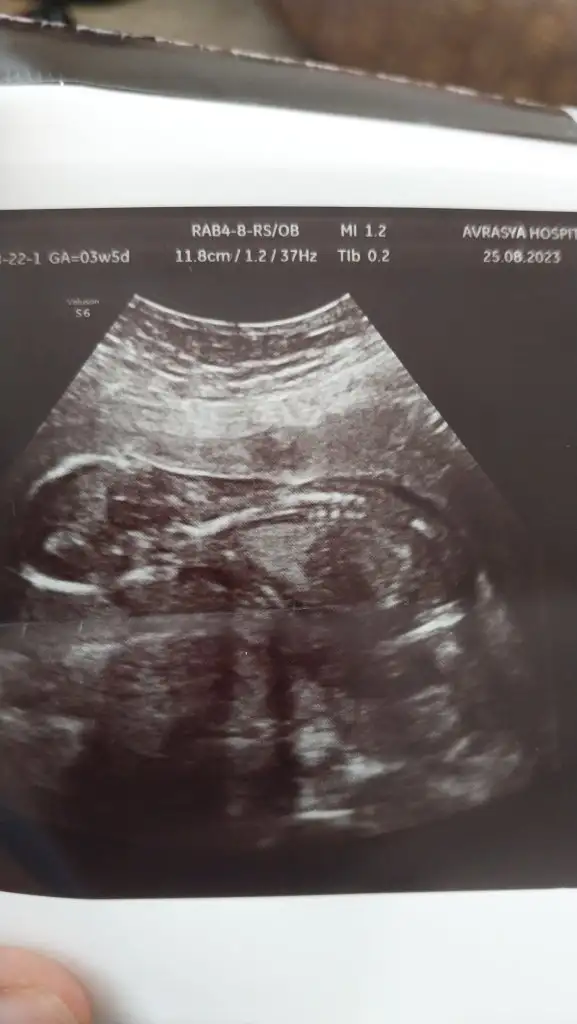

Merhaba lar hanımlar ilk 2 resim 11 haftalikken diğer resimlerde 15 haftalikken banada tahminde bulunurmusunuz